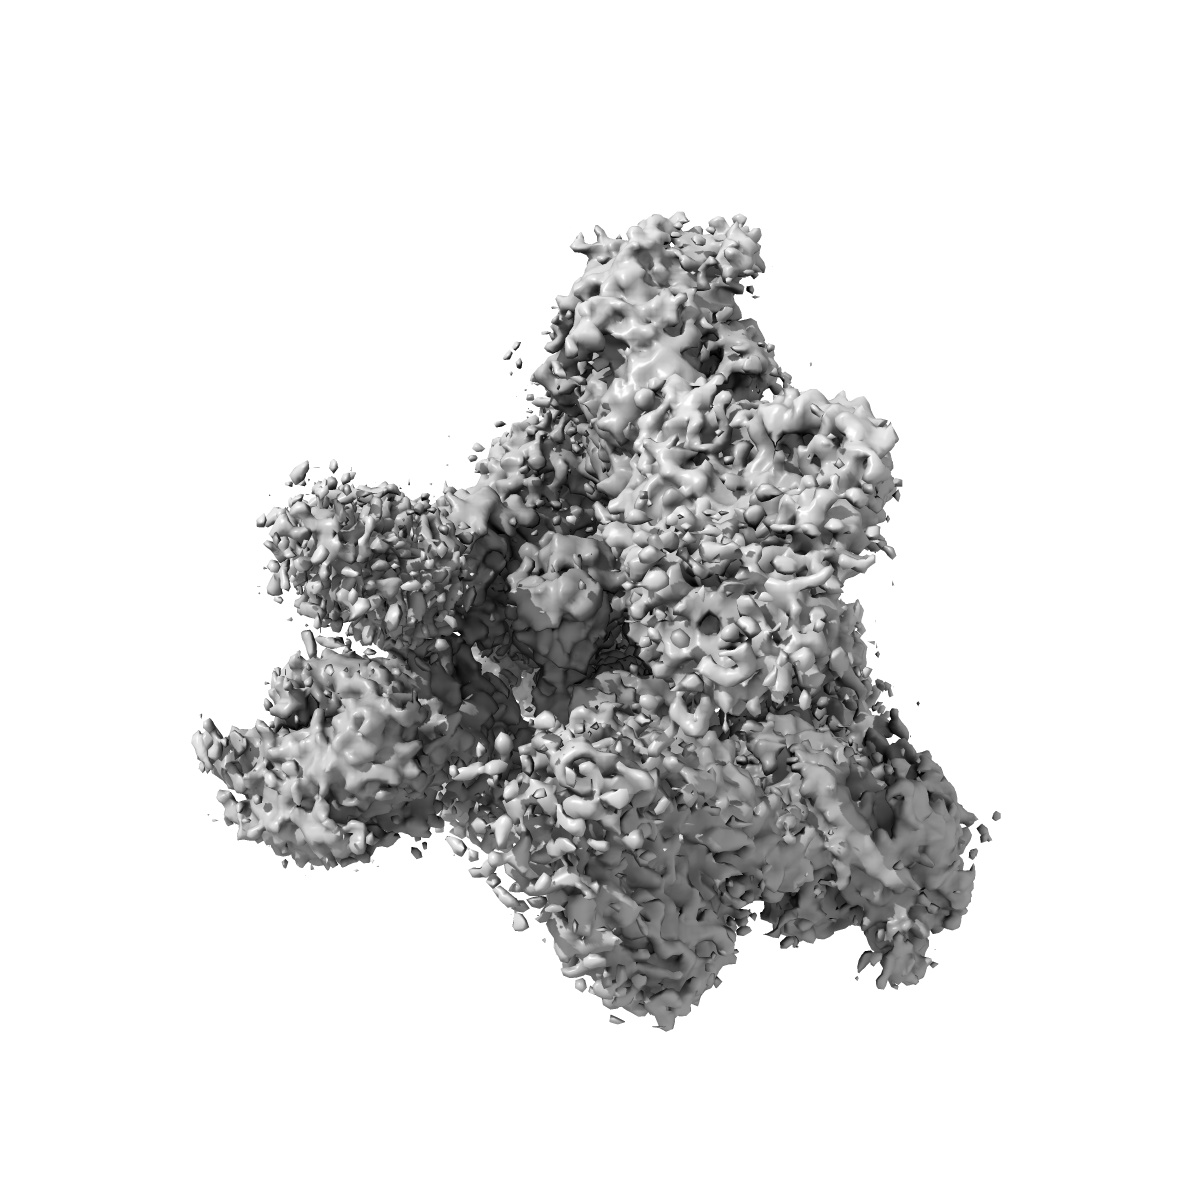

S728-1157 IgG in complex with SARS-CoV-2-6P-Mut7 Spike protein (global refinement)

Single-particle3.3 Å

Sample: S728-1157 IgG in complex with SARS-CoV-2-6P-Mut7 S protein